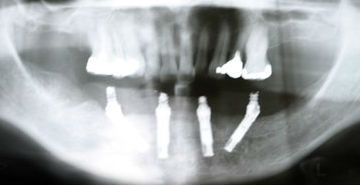

This technique strategically places four dental implants into the anterior (front) portion of the jaw, where bone density is typically more preserved.

By angling the posterior implants, they create a strong base for a full-arch prosthetic.

- Shorter, angled implants require precise surgical planning